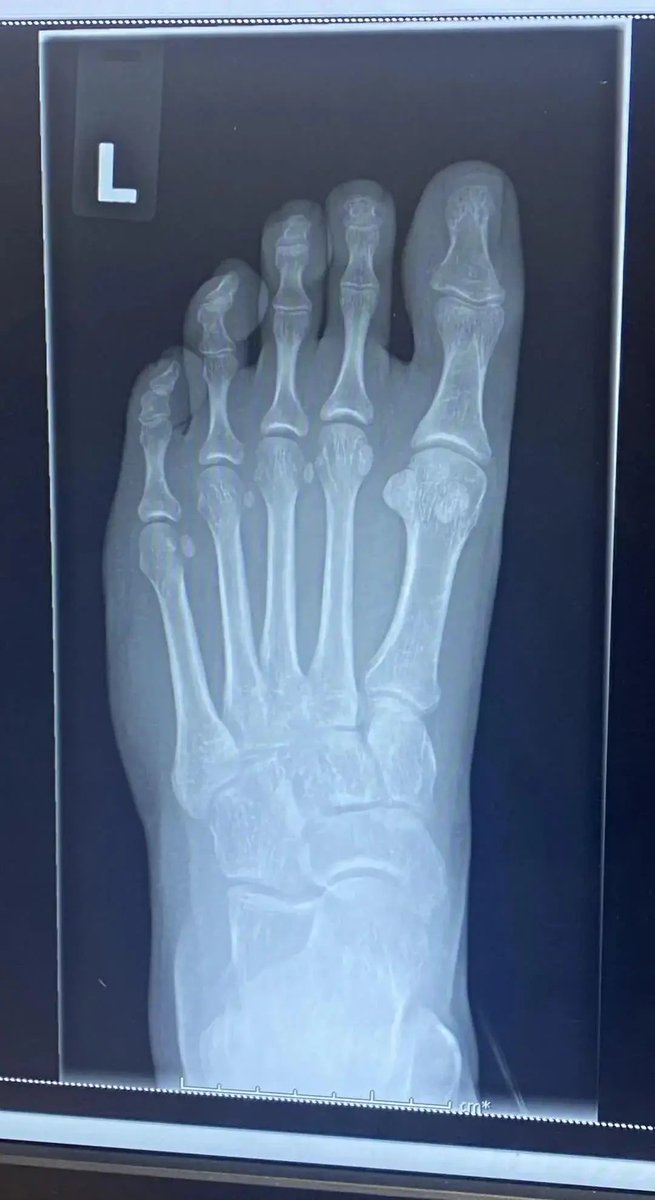

Doctor: “Do you want to see something strange I’ve never seen before?” “Have you ever seen an X-ray of your feet before? I need to show you something strange”. She told me that everyone has Sesamoid bones in their big toes but she has never seen someone with the bones in all